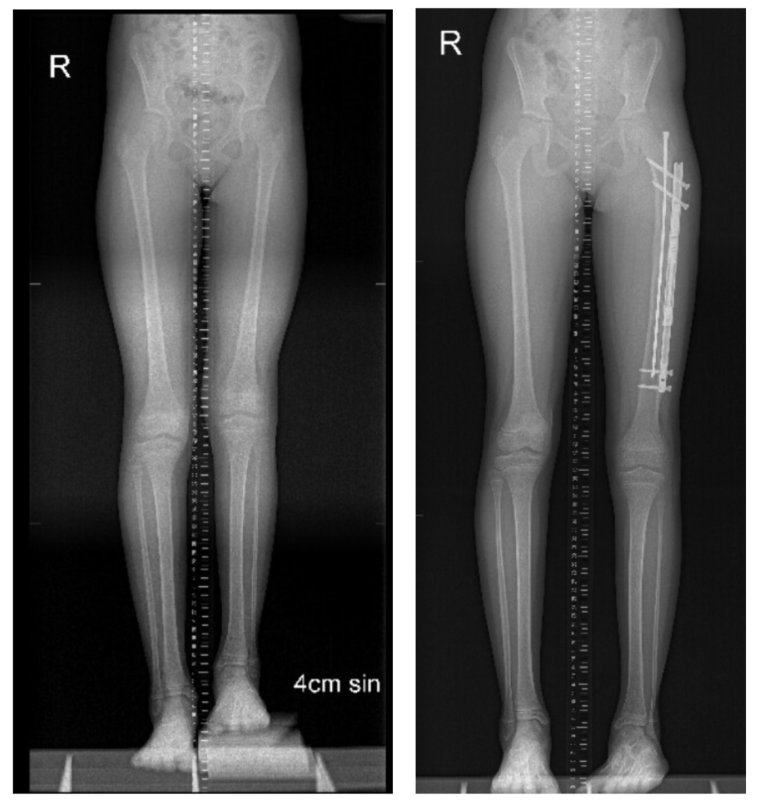

První případem prodloužení kosti za pomoci magnetického hřebu uloženého mimo dřeňovou dutinu kosti v České republice, byla osmiletá Lucie s vrozenou krátkou stehenní kostí. Před operací měla nohu kratší o 4,5 cm. Hřeb s magnetem byl zaveden v říjnu roku 2022, za dva měsíce byla kost prodloužena o 5 cm, následující rok v srpnu byl hřeb vyjmut a léčba byla ukončena. „Lucinka měla od malička problémy s nožičkama, musela nosit řemínky a ve věku tří let jsme zjistili, že má kratší nožičku. Jsme šťastní, že to dobře dopadlo, jsme vděční, za operaci touto metodou. Samotné protahování nebolelo, náročné bylo cvičení, a to i na psychiku,“ říká maminka Eliška Sedlářová.

Další případ vrozeného zkrácení kosti s prodloužením pomocí magnetického hřebu řešili lékaři FN Brno v srpnu 2023. Jsme rádi, že jsme mohli být ve FN Brno jedni z prvních na světě v aplikaci této revoluční metody, a že se stane tato metoda pro děti s vrozeným i získaným zkratem končetiny standardní.